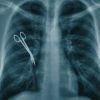

Да, медики научились творить чудеса, пересаживая сердце или спасая новорожденных. Особенно больших успехов добилась хирургия. Но, увы, все эти чудеса науки и техники сводятся на нет безответственностью медработников, их равнодушием и алчностью…